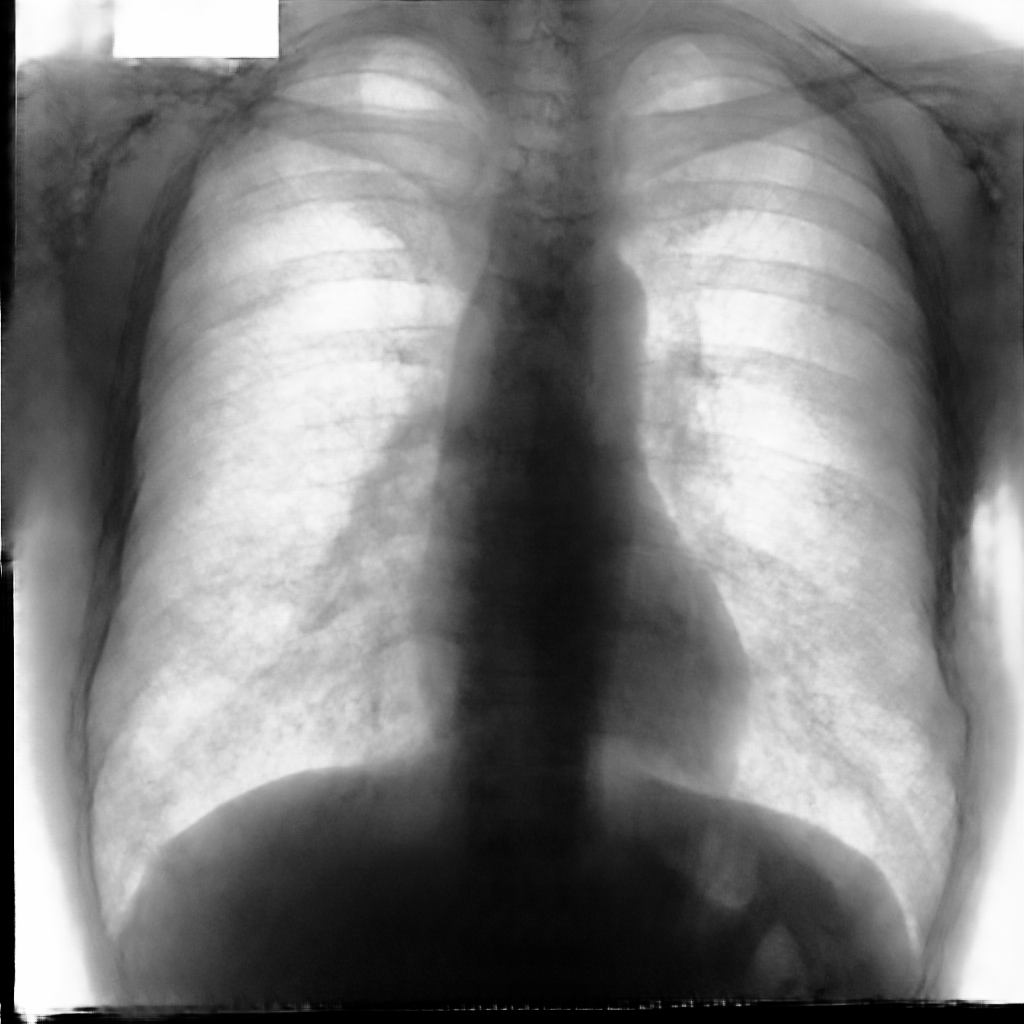

In this section, some examples of images and corresponding segmentations, generated with the approaches described in Section 3, are qualitatively examined. We also report some comments from three physicians on the generated segmentations, to provide a medical assessment of the quality of our method.

Figure 5 and Figure 6 display some examples — randomly chosen from all the generated images — of the label–maps and the corresponding chest X–ray images generated with the three methods described in Section 3, using the FULL_DATASET and the TINY_DATASET, respectively. We can observe that, with the single and two–stage methods, the images tend to be more similar to those belonging to the training set. For example, in most of the generated images there are white rectangles, which resemble those present in the training images, used to cover the names of both the patient and the hospital. Instead, the three–stage method does not produce such artifacts, suggesting that it is less prone to overfitting.

Moreover, in order to clarify the limits of the three–stage method, we assessed the quality of the segmentation results based on three human experts, who were asked to check 20 chest X–ray images, along with the corresponding supervision and the segmentation obtained by the SMANET network. Such images were chosen among those that can be considered difficult, at least based on the high error obtained by the segmentation algorithm. Figure 7 and Figure 8 show different examples of the images evaluated by the experts. The first column represents the chest X–ray image, while the second and the third columns, whose order was randomly exchanged during the presentation to the experts, represent the target segmentation and our prediction, respectively. The three physicians were asked to choose the best segmentation and to comment about their choice. Apart from a general agreement of all the doctors on the good quality of both the target segmentation and the segmentation provided by the three–stage method, surprisingly, they often chose the second one. For the examples in Figure 7, for instance, all the experts share the same opinion, preferring the segmentation obtained by the SMANET over the ground–truth segmentation. To report the results of the qualitative analysis, we numbered the target and predicted segmentation with 1 and 2, respectively, while doctors were assigned unordered pairs to obtain an unbiased result. Then, with respect to Figure 7(a), the comments reported by the experts were: 1) In segmentation 1, a fairly large part of the upper left ventricle is missing; 2) I choose the segmentation number 2 because the heart profile does not protrude to the left of the spine profile; 3) The best is No. 2, the other leaves out a piece of the left free edge of the heart, in the cranial area. Instead, for Figure 7(b), we obtained: 1) The second image is the best for the cardiac profile. For lung profiles, the second image is always better. The only flaw is that it leaks a bit on the right and left costophrenic sinuses. 2) Image 2 is the best, because the lower cardiac margin is lying down and does not protrude from the diaphragmatic dome. Image number 1 has a too flattened profile of the superior cardiac margin. 3) No. 2 for the cardiac profile more faithful to the real contours.